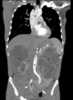

Polycystic kidneys and liver

Polycystic kidney disease (PKD or PCKD, also known as polycystic kidney syndrome) is a genetic disorder in which the renal tubules become structurally abnormal, resulting in the development and growth of multiple cysts within the kidney. These cysts may begin to develop in utero, in infancy, in childhood, or in adulthood. [Source: Wikipedia ]